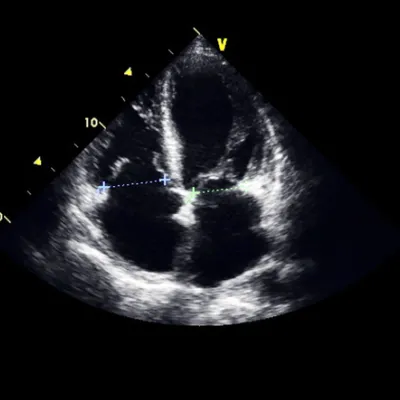

Transesophageal Echocardiogram

A transesophageal echocardiogram, sometimes abbreviated as a TEE is a specialized ultrasound of the heart.

A transesophageal echocardiogram, sometimes abbreviated as a TEE is a specialized ultrasound of the heart.